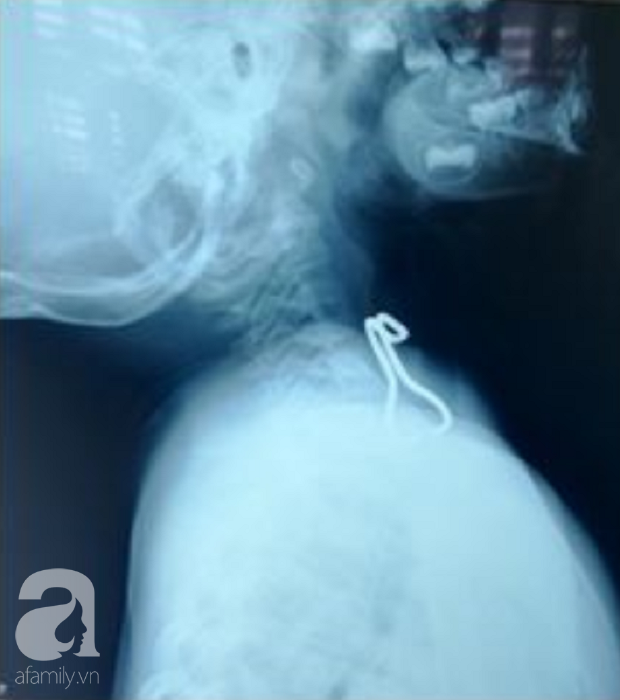

03/08/2018 15:13Nghệ An: Cầm móc sắt chơi rồi nuốt vào miệng, bé trai 26 tháng tuổi thủng thực quản

Đó là trường hợp của bé Đặng Thái K. (26 tháng tuổi, ngụ tỉnh Nghệ An), nhập viện vì nuốt móc sắt.

Theo lời người nhà khai, trong lúc chơi đùa bé tự lấy cái móc sắt rồi bất ngờ đưa vào miệng. Bệnh nhi sau đó nôn ói, đau vùng cổ, không ăn uống được. Khi đến khám tại BV địa phương, ảnh chụp X - quang nghi ngờ có dị vật cản quang vùng thực quản nên bé được chuyển đến bệnh viện (BV) Nhi Đồng 1 (TP.HCM).

Tại đây, ekip điều trị tiến hành gây mê soi cấp cứu trong đêm, gắp được chiếc móc sắt dài gần 4cm ở miệng thực quản. Sau khi hồi tỉnh 3 giờ, bé đã có thể uống sữa và sau đó ăn cháo bình thường, không còn nôn ói, hết đau.